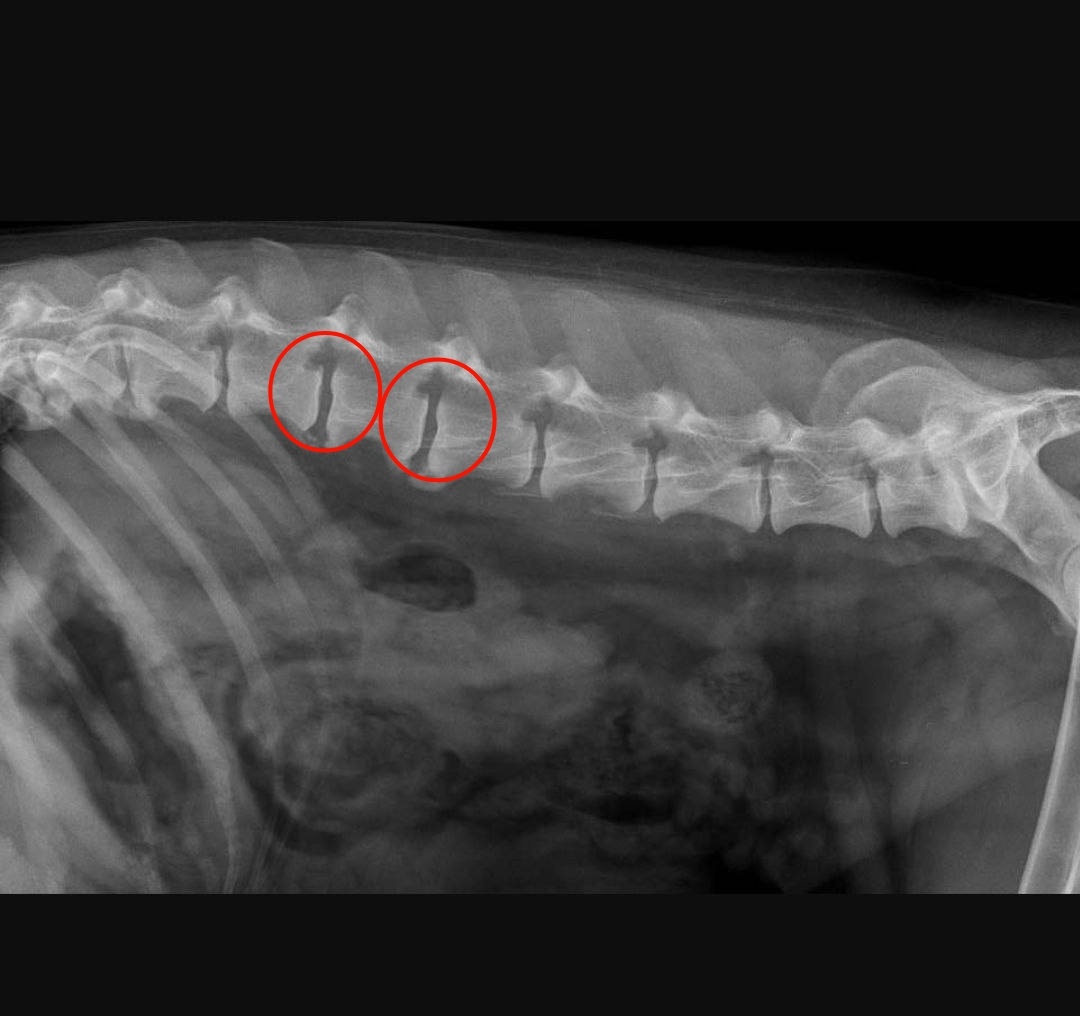

Спондилез

Дегенеративное заболевание позвоночника, характеризующееся образованием костных разрастаний на позвонках.

Такие разрастания могут сдавливать нервные корешки, вызывая боль и нарушение чувствительности в конечностях.

Спондилез позвонков